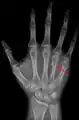

A fracture of the fourth and/or fifth metacarpal bones transverse neck secondary due to axial loading is known as a boxer's fracture.[1]

A fractured right hand fourth metacarpal (boxer's fracture).